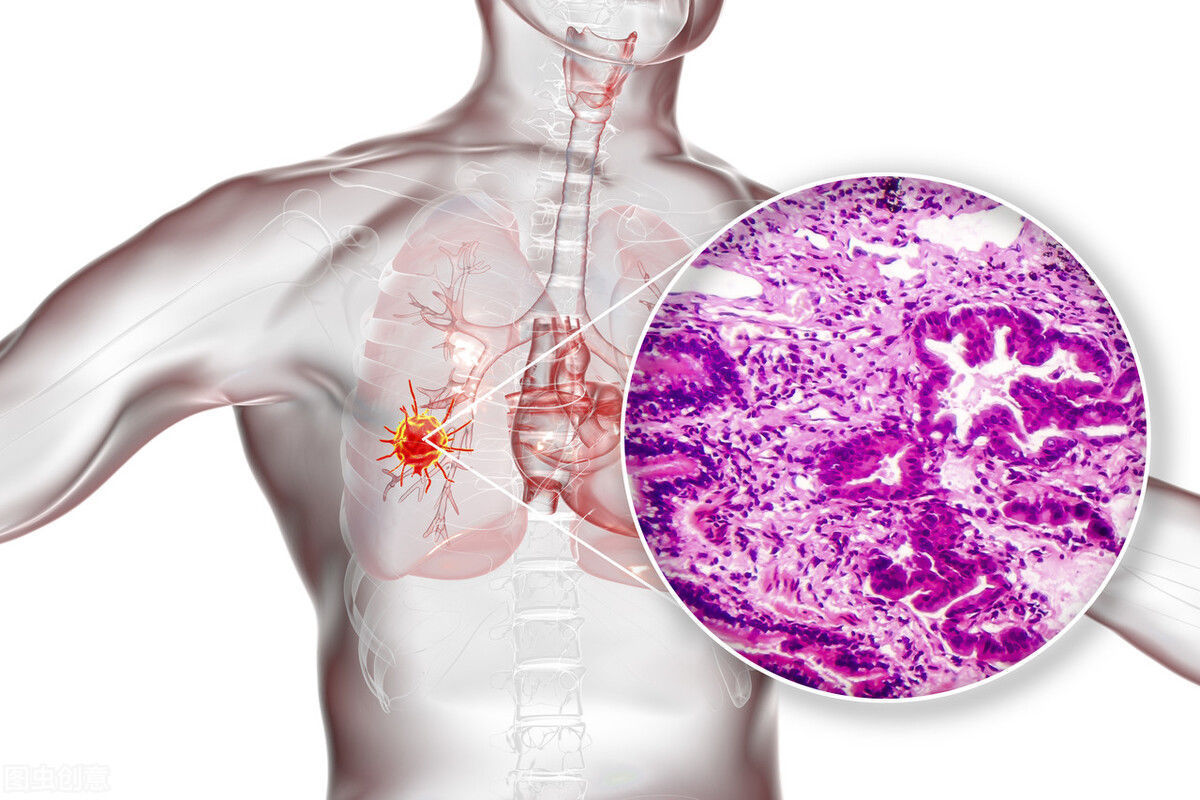

3. 肺癌,结节边缘毛呈滑裂小叶状,密度不均,在短时间内迅速生长,有明显的体征及症状。也可结肠癌及颅内肿瘤肺转移。

4. 肺良性肿瘤,如肺纤维瘤、肺无组织肿瘤等。